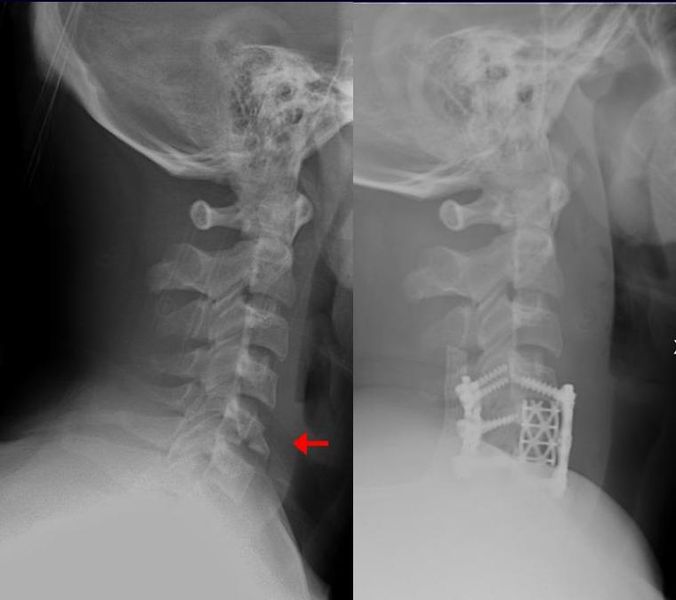

Spinal Fracture

Many spinal fractures heal without causing paralysis despite their severity

What is the primary factor that determines the risk of spinal cord injury following a spinal fracture?

The age of the patient at the time of injury

The location of the fracture in the cervical spine always causes paralysis

Whether the fracture is stable or unstable